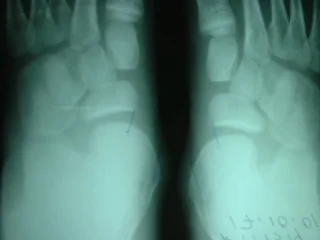

Preoperatorio